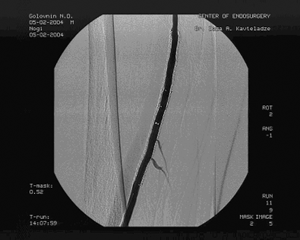

Доступом в подколенной области выделена подколенная артерия слева, перевязано артериовенозное соустье, пунктирована подколенная артерия и произведена баллонная ангиопластика стенозов левой ПБА с хорошим непосредственным результатом, не потребовавшая дополнительного стентирования. (см. рис. 5)

Рис. 5. Контрольная ангиография после ЧТА левой ПБА.

Пациент выписан на 4-e сутки с клиническим выздоровлением и повышением ПЛИ до 0,89.